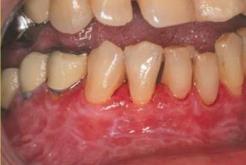

Az összes klinikai forma érintheti a gingivát, más intraorális területek megbetegedése nélkül. Az esetek kb. 10%-a csak a gingiván okoz tüneteket, a lichen a desquamativ gingivitis leggyakoribb oka. Ez megnehezítheti a diagnózist. A gingiva felépítése nehézzé teszi biopsiás anyag nyerését és a szöveti struktúra nehézzé teszi a szövettani eredmény interpretálását, különösen, ha a képet nem specifikus gingivitis is komplikálja. A gingiva ilyenkor teljes szélességében fénylő, vörös. Ezt a formát desquamativ gingivitisnek nevezik, ami más autoimmun betegségek szájtünete is lehet (11.8. ábra).

11.8. ábra. Gingivalis lichen oris (desquamativ gingivitis)